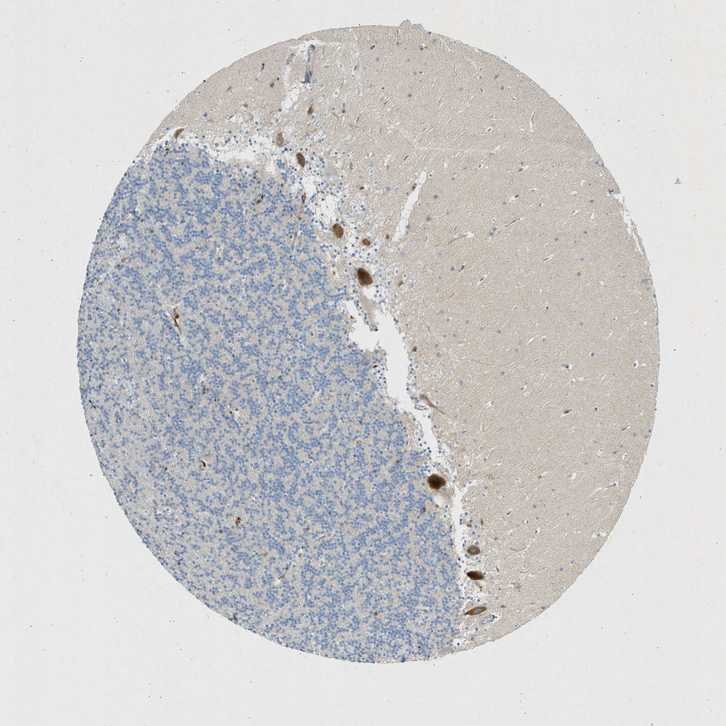

CEREBELLUM - Antibody stainingi

Antibody staining in the annotated cell types in the current human tissue is reported as not detected, low, medium, or high, based on conventional immunohistochemistry profiling in selected tissues. This score is based on the combination of the staining intensity and fraction of stained cells.

Each image is clickable and will lead to virtual microscopy that enables deeper exploration of all samples and also displays staining intensity scores, fraction scores and subcellular localization as well as patient and tissue information for each sample.

Antibody HPA051476Antibody HPA054698Antibody CAB016780

Purkinje cells MediumNot detectedHigh

Cells in granular layer LowNot detectedNot detected

Cells in molecular layer Not detectedNot detectedNot detected